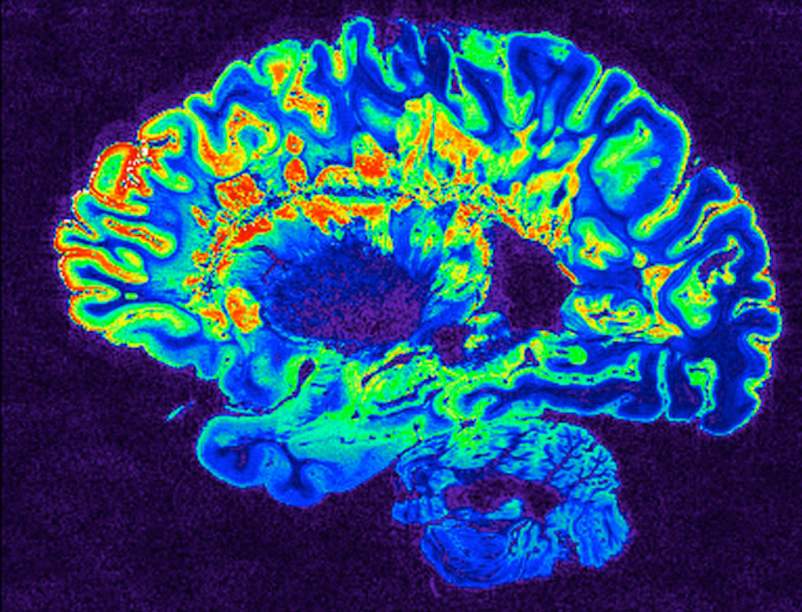

我们知道,多发性硬化症是一种自身免疫性疾病时,身体会错误的攻击髓鞘发生,环绕在大脑和脊髓的神经保护层。受损的区域称为斑块或病变。

所有的多发性硬化症患者都在脊髓和脑部发生病变。弗拉纳根博士解释说,这些病变的严重程度不同,医生可以通过磁共振成像(MRI)监测疾病进展。

对于患有多发性硬化症的人来说,他们的脑部MRI有很多活跃的病变,但没有新的症状是很常见的。弗拉纳根博士说,这可能与病变发生的位置有关。你的中枢神经系统有三个区域受到多发性硬化症的影响:脊髓、大脑和视神经。

在大脑中的神经更分散相比,脊髓或眼内,在那里它们更压实的神经。当病灶在大脑中的发展,您可能没有症状的时候了。但是,你更有可能从对脊髓病变的症状,弗拉纳根博士说。